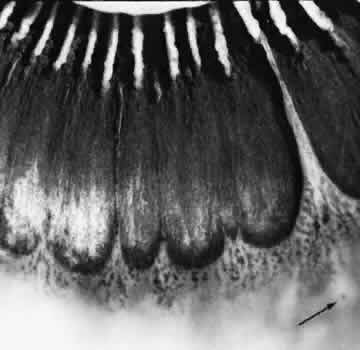

degeneration (Fig. 8).  Fig. 8. Meridional fold in a young patient. Retina is thickened along course of

fold, which shows microcystoid change near the surface and a cap of dense-staining

glial cells along its surface. Middle and outer layers of

the retina are largely unremarkable. Pigment epithelium shows focal

redundancy anteriorly. (Hematoxylin-eosin; × 150.) Fig. 8. Meridional fold in a young patient. Retina is thickened along course of

fold, which shows microcystoid change near the surface and a cap of dense-staining

glial cells along its surface. Middle and outer layers of

the retina are largely unremarkable. Pigment epithelium shows focal

redundancy anteriorly. (Hematoxylin-eosin; × 150.)